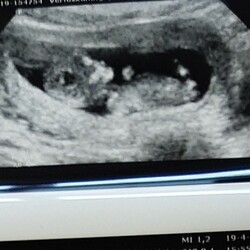

Hier helaas ongeveer hetzelfde. Vandaag eerste echo met 7+3 en iets kleiner vruchtje met een trage hartslag....

Volgende week weer een echo met hopelijk een goede uitkomst.